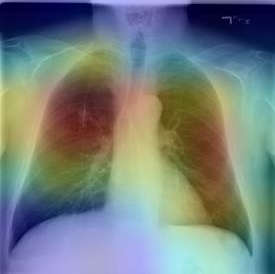

The COVID-19 disease was first discovered in Wuhan, China, and spread quickly worldwide. After the COVID-19 pandemic, many researchers have begun to identify a way to diagnose the COVID-19 using chest X-ray images. The early diagnosis of this disease can significantly impact the treatment process. In this article, we propose a new technique that is faster and more accurate than the other methods reported in the literature. The proposed method uses a combination of DenseNet169 and MobileNet Deep Neural Networks to extract the features of the patient's X-ray images. Using the univariate feature selection algorithm, we refined the features for the most important ones. Then we applied the selected features as input to the LightGBM (Light Gradient Boosting Machine) algorithm for classification. To assess the effectiveness of the proposed method, the ChestX-ray8 dataset, which includes 1125 X-ray images of the patient's chest, was used. The proposed method achieved 98.54% and 91.11% accuracies in the two-class (COVID-19, Healthy) and multi-class (COVID-19, Healthy, Pneumonia) classification problems, respectively. It is worth mentioning that we have used Gradient-weighted Class Activation Mapping (Grad-CAM) for further analysis.

翻译:COVID-19 疾病在中国武汉首次发现,并迅速蔓延到全世界。在COVID-19 流行病后,许多研究人员开始寻找一种方法,利用胸前X光图像诊断COVID-19 。早期诊断该疾病可以大大影响治疗过程。在本篇文章中,我们提出了一种比文献中报告的其他方法更快和更准确的新方法。拟议方法使用DenseNet169 和移动网络深神经网络的组合来提取病人X光图像的特征。在使用单向特征选择算法后,我们改进了最重要的特征。然后,我们将选定特征用作对光GBM(轻度推动机)算法的投入。为评估拟议方法的有效性,使用了ChestX-光8 数据集,其中包括病人胸部的1125 X光图像。拟议方法在两类(COVID-19,健康价值)和多级(COVID-19)中达到了98.54%和91.11%的缩略图。我们分别使用了“高度”的GRAMA-GRA级(C) 分别用于健康等级分析。